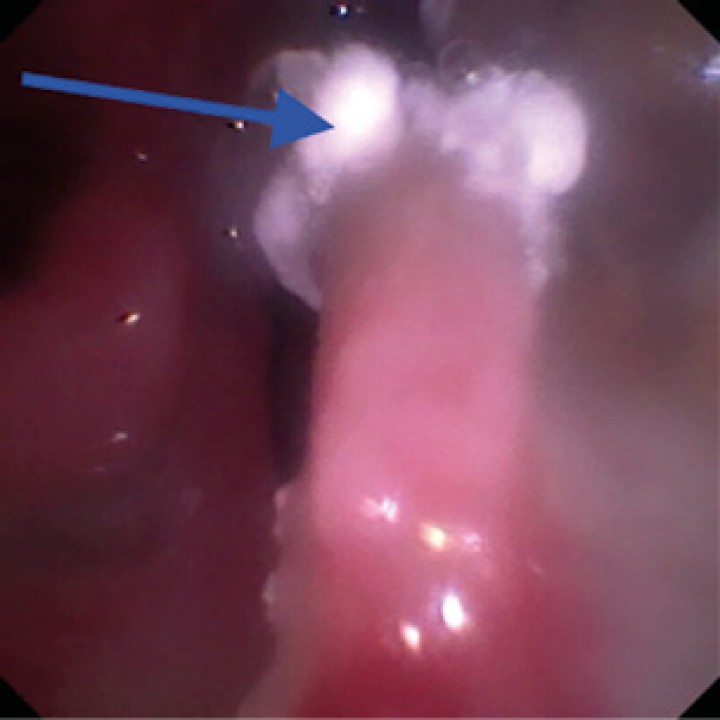

Tras el primer tratamiento los signos clínicos se mantuvieron, por lo que se realizó una segunda rinoscopia a las 3 semanas, observándose una mejoría respecto a la anterior, pero aún presentaba pequeñas placas fúngicas (Fig. 4).

Rinoscopia de control tras 3 semanas del primer tratamiento con crema antifúngica. Se observan pequeñas placas (flecha azul).